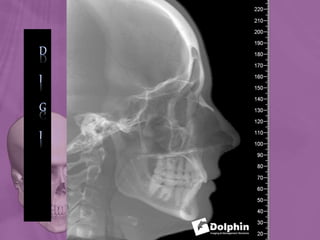

Lateral Cephalogram

 Although the cephalometric radiograph in standard

lateral projection was introduced into orthodontics

during 1930s, the method has become routine in recent

years.

 Today cephalometric analysis has firmly taken place in

dentofacial diagnostic procedures.